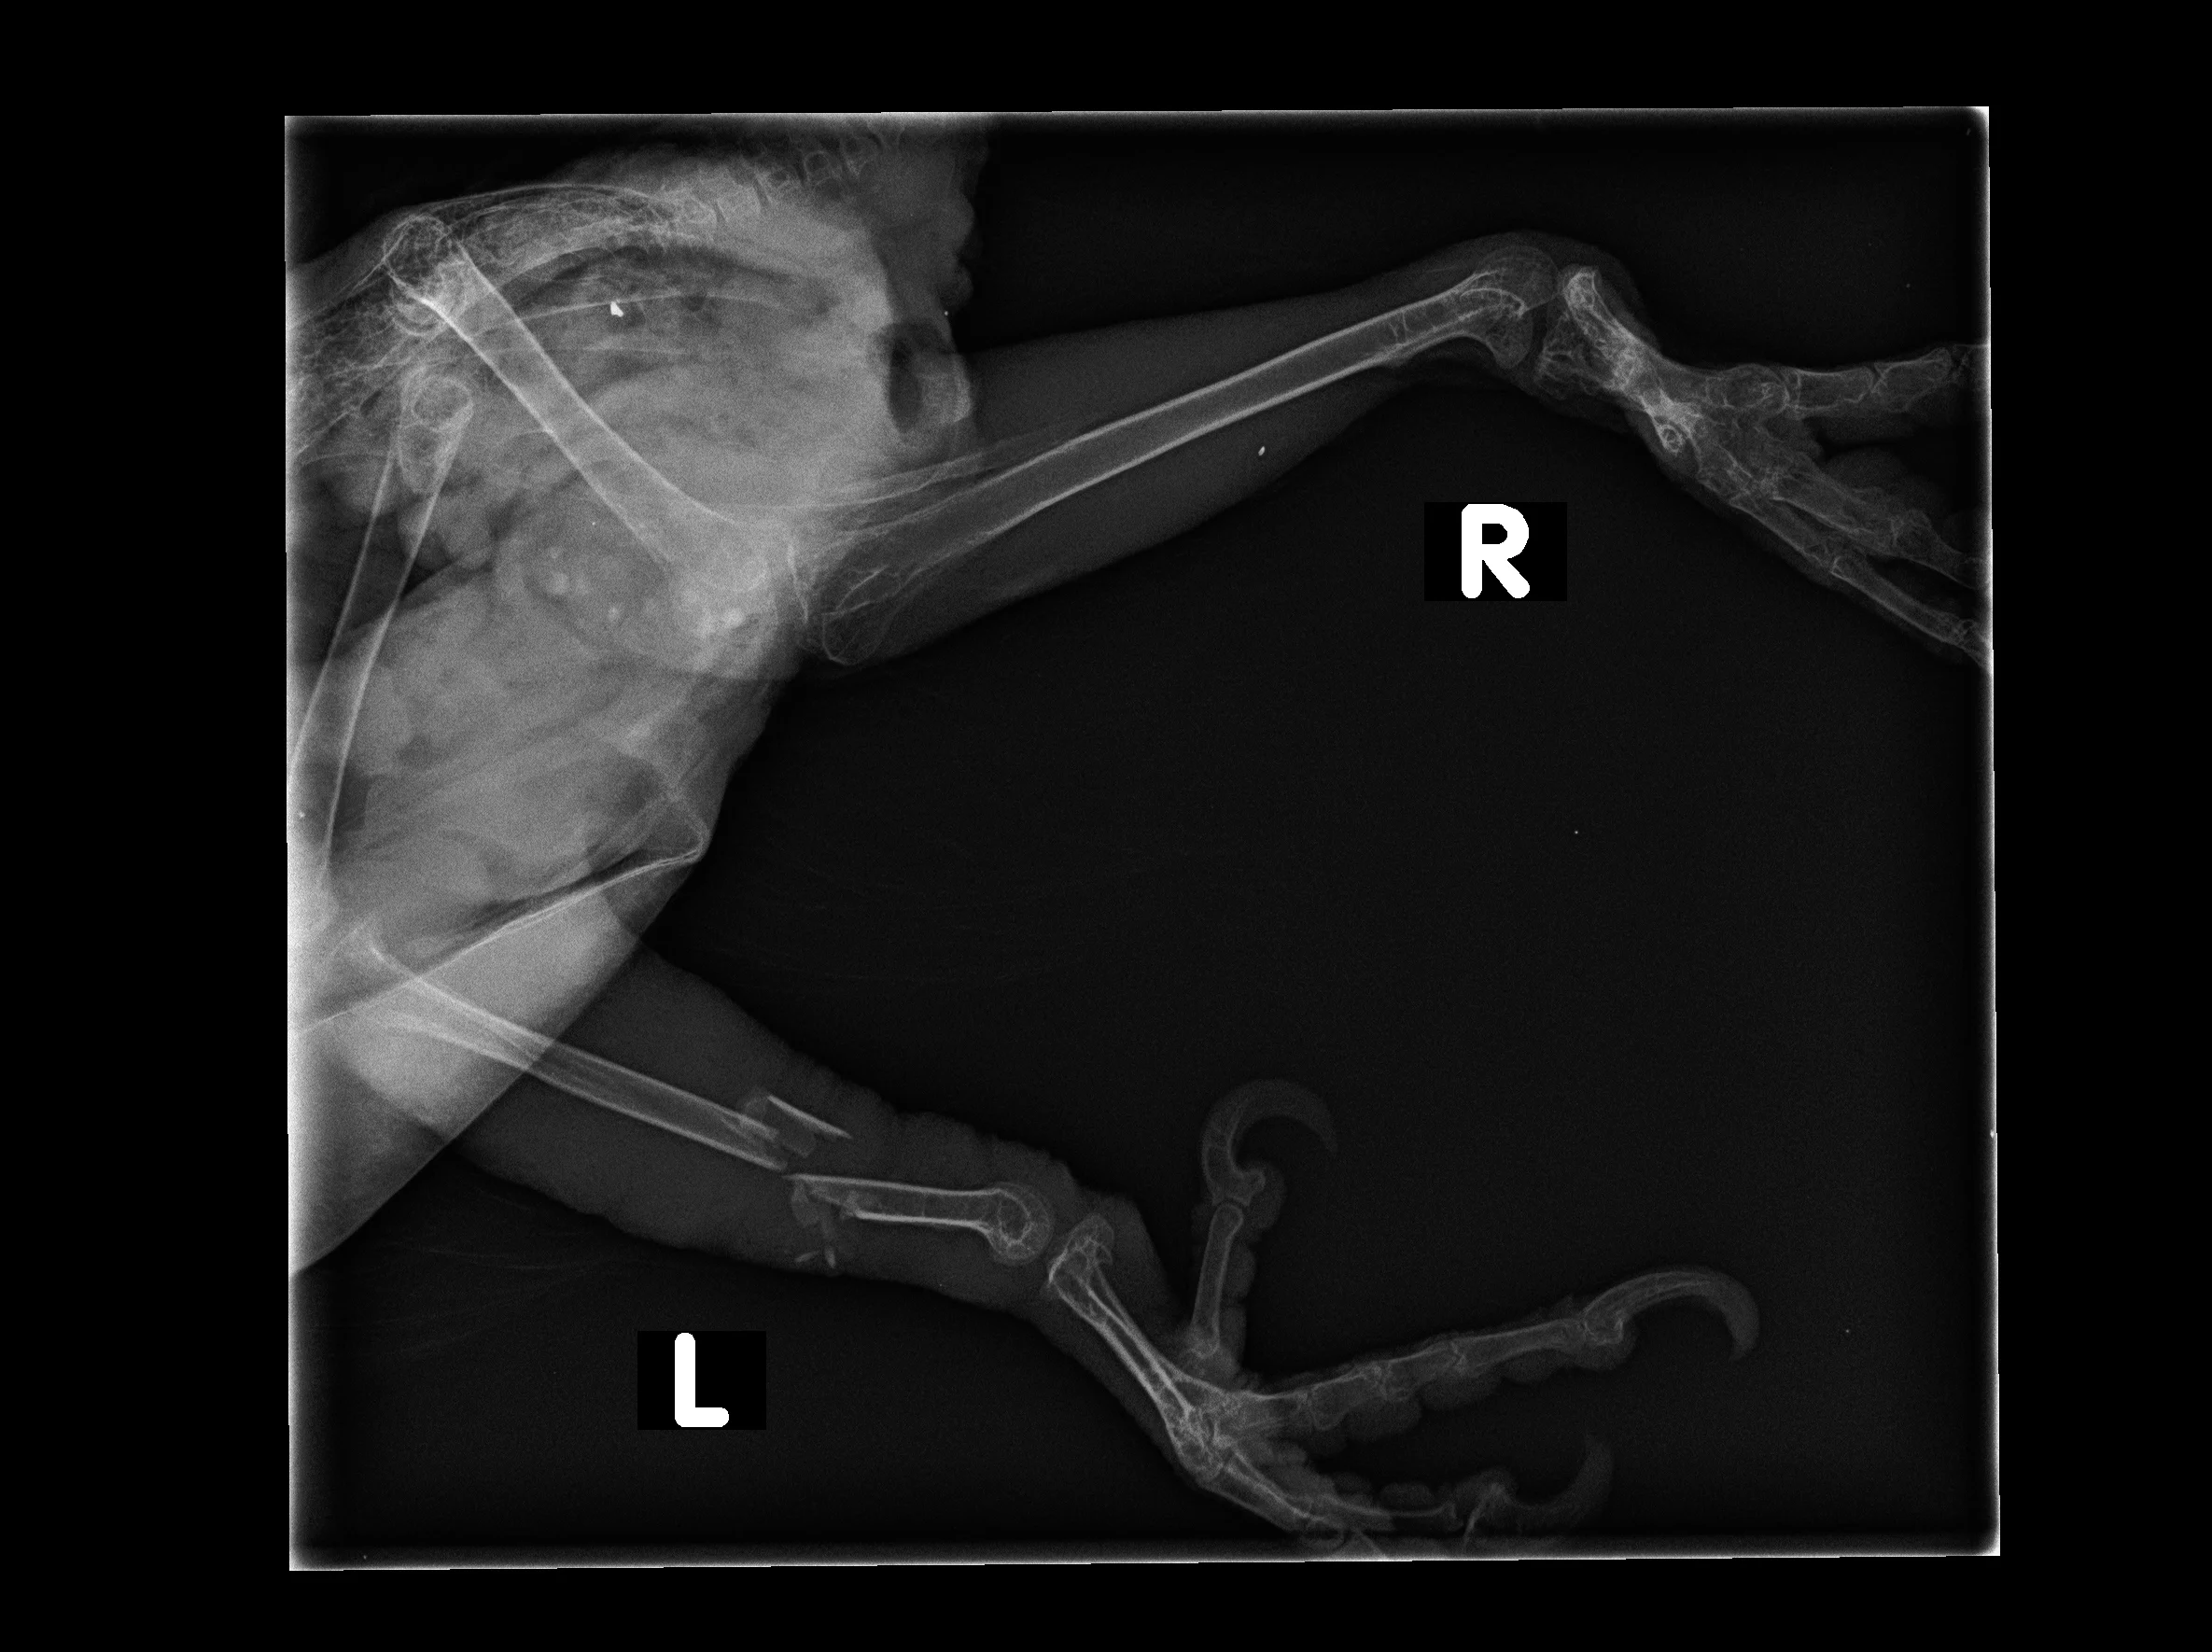

2. Trauma, especially from other pets like dogs and cats. The bacteria from the claws and teeth of cats can be especially dangerous, and even a very small puncture can mean a severe infection and possibly death in just a few days. Predators and parrots should never be unsupervised. Many owners tell us they did not expect the attack the pets had appeared to get along prior.